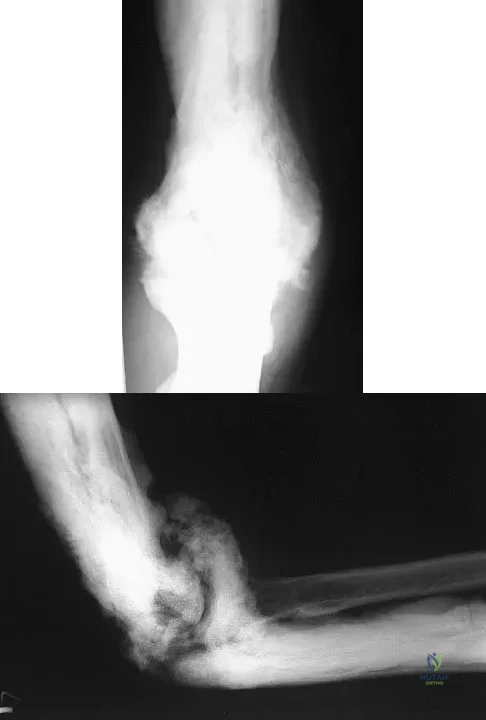

A 35-year-old man has atraumatic painless limited elbow motion. Radiographs are shown in Figures 33a and 33b. What is the most likely diagnosis?

Explanation:

Based on the radiographic findings, the patient has melorheostosis, a rare, benign connective tissue disorder that is characterized by a cortical thickening of bone. It produces a "dripping candle wax" appearance with dense hyperostosis that flows along the cortex. Ectopic bone formation is a consideration but is associated with injuries or burns. Bone infarcts produce intraosseous sclerosis typically affecting the distal femur with the "smoke up chimney" appearance. Infection is always a consideration but typically does not have the linear osteitis seen in melorheostosis. Juxacortical chondroma is a benign cartilage growth that arises from the capsule and may involve the underlying cortical bone but rarely the medullary canal. Campbell CJ, Papademetriou T, Bonfiglio M: Melorheostosis: A report of the clinical, roentgenographic, and pathological findings in fourteen cases. J Bone Joint Surg Am 1968;50:1281-1304.